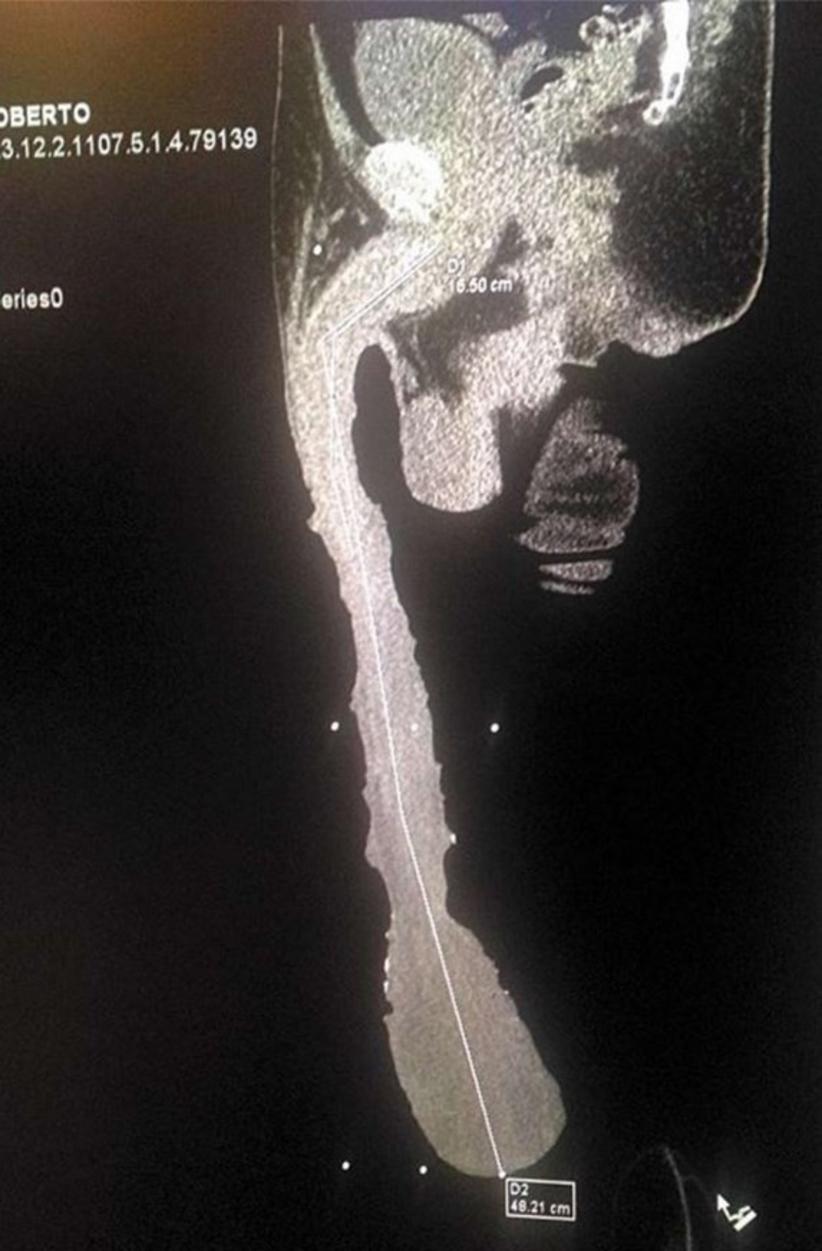

Roberto Esquivel Cabrera, o homem que possui o maior pênis do mundo, com 48.2 centímetros, pretende seguir carreira pornô.